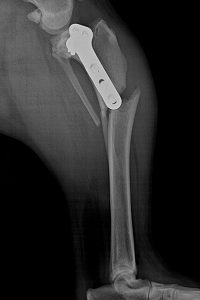

Golden Retriever Bella schien wie vom Pech verfolgt. 2016 zog sich die schöne Hündin im Abstand weniger Monate zwei Kreuzbandrisse zu, die in der Tierklinik Ismaning per TPLO chirurgisch versorgt wurden. Alles verheilte gut, und Bella konnte nach den entsprechenden Schonzeiten ihre Kniegelenke wieder voll belasten. Doch dann wurde sie im Januar 2018 von einem Auto angefahren, und ihr linker Unterschenkel brach genau unterhalb der Knochenplatte, die Bella im Rahmen der TPLO zur Knochenstabilisierung eingesetzt worden war (Röntgenbild ganz rechts). Bellas Frauchen befürchtete schon das Schlimmste. Doch unser Chefarzt Dr. Klaus Zahn konnte Bellas Beinchen wieder vollständig herstellen. Bei OP Nummer drei entfernte er die alte Platte und verschraubte eine neue im Knochen. Die Folge: Heute rennt, läuft und spielt Bella, als ob nie etwas gewesen wäre.